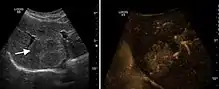

HCC appearance on 2D ultrasound is that of a solid tumor, with imprecise delineation, with heterogeneous structure, uni- or multilocular (encephaloid form). An "infiltrative" type is also described which is difficult to discriminate from liver nodular reconstruction in cirrhosis. Typically HCC invades liver vessels, primarily the portal veins but also the hepatic veins . Doppler examination detects a high speed arterial flow and low impedance index (correlated with described changes in tumor angiogenesis). The spatial distribution of the vessels is irregular, disordered. CEUS examination shows hyperenhancement of the lesion during the arterial phase. During the portal venous phase there is a specific "wash out" of ultrasound contrast agent (UCA) and the tumor appears hypoechoic during the late phase. Poorly differentiated tumors may have a stronger wash out leading to an isoechoic appearance to the liver parenchyma during portal venous phase. This appearance was found in approx. 30% of cases. The described changes have diagnostic value in liver nodules larger than 2 cm.

Ultrasound is useful in HCC detection, stadialization and assessing therapeutic efficacy. In terms of staging related to therapy effectiveness, the Barcelona classification is used which identifies five HCC stages. Curative therapy is indicated in early stages, which include very early stage (single nodule <2 cm), curable by surgical resection (survival 50-70% five years after surgical resection) and early stage (single nodule of 2–5 cm, or up to 3 nodules <3 cm) which can be treated by radiofrequency ablation (RFA) and liver transplantation. Intermediate stage (polinodular, without portal invasion) and advanced stage (N1, M1, with portal invasion) undergo palliative therapies (TACE and sorafenib systemic therapy) and in the end stage only symptomatic therapy applies.